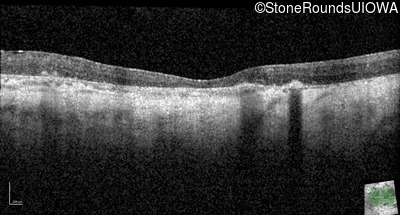

Optical Coherence Tomography - Right - No Light Perception

Exemplar / OCT Stack

Optical Coherence Tomography - Left - Light Perception